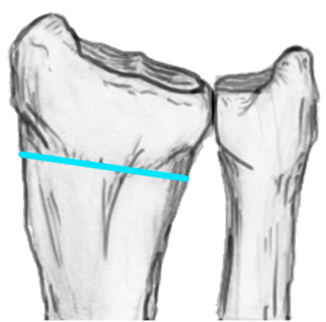

1. Distal radial Step > 2mm

- leads to RC OA radiographically

2. Articular incongruency sigmoid notch / DRUJ > 2 mm

3. Radial shortening > 5 mm

- leads to ulnocarpal abutment